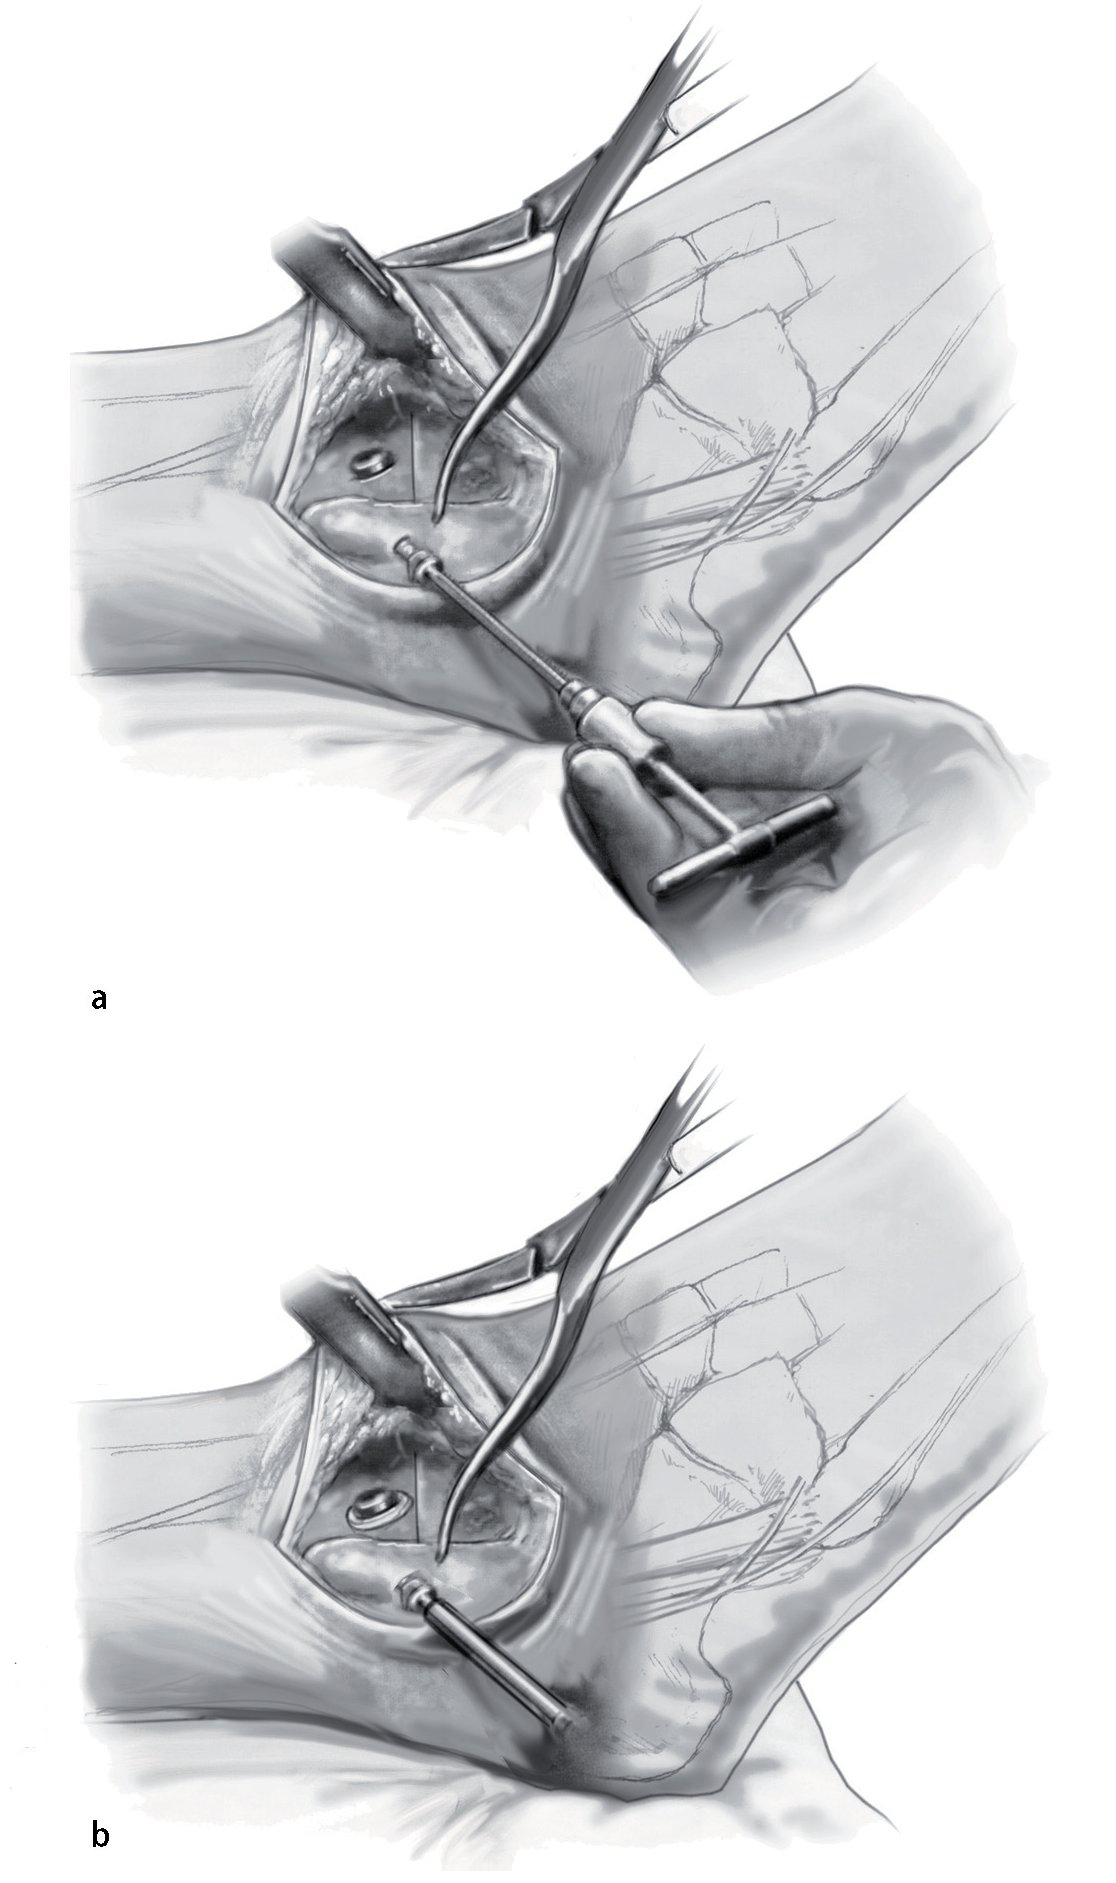

Fig. 9 Compruebe la alineación y aplique fijación provisionalmente con el uso de dos pinzas Weber grandes. Asegurarse de que el astrágalo esté colocado un poco posterior respecto al margen distal de la tibia anterior para reducir así el brazo de palanca anterior del pie.

Fig. 10 Utilice la broca de 2,5 mm y un gubia de 1 cm para extraer un triángulo de capa cortical en el lado anteromedial de la tibia. La base del triángulo debe ser paralela a la planta del pie. Eso permite el avellanado, así como un posicionamiento más pendiente del tornillo respecto a la tibia.

Fig. 11 Mediante el uso de una broca de deslizamiento/broca guía de 4,5 mm se realizan agujeros en sentido medial y lateral, seguidos de agujeros de 3,2 mm con rosca en la capa cortical opuesta. Se colocan dos tornillos corticales de fijación de 4,5 mm con rosca completa y arandelas. El tornillo medial se dirige un poco en dirección anterior, mientras que el tornillo lateral se orienta ligeramente más posterior. Lo ideal es que el tornillo cruce craneal al nivel de la osteotomía.

Fig. 12 Se retiran las pinzas Weber. El peroné distal se vuelve girar a su posición. Se fija una pinza Weber sobre él para obtener reducción temporal. La fijación final se logra mediante un tornillo cortical de fija ción con rosca completa de 4,5 mm.